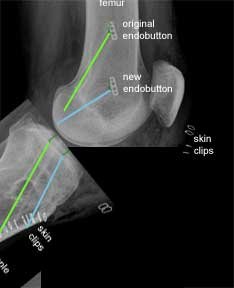

This is an X-ray, of the same patient, taken from the side instead of the front. The green lines show the original tunnels and the blue lines the new tunnels.

For the femoral tunnels the higher endobutton is from the original procedure and the lower endobutton is from the revision procedure.

The new tibial tunnel (blue) is more anterior (closer to the front) than the original tunnel. This is a more anatomic position for the tibial insertion of the native ACL.